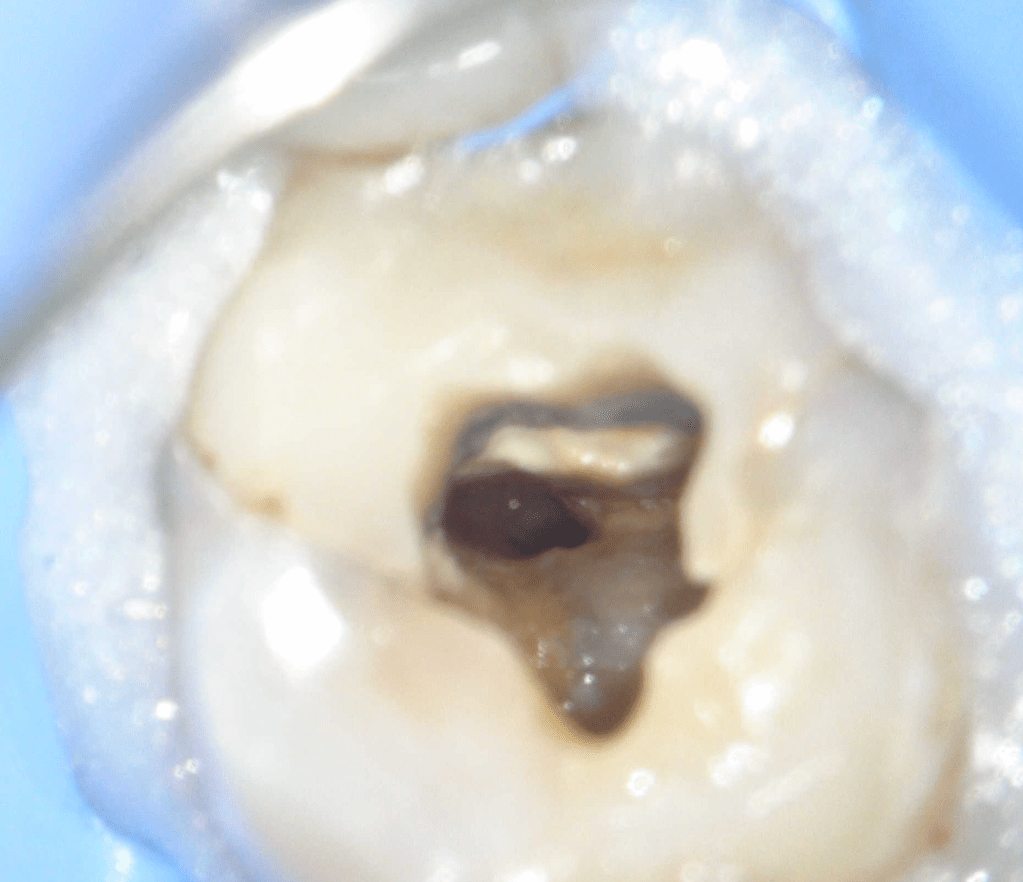

Reco preendo + 4 conductos molar superior